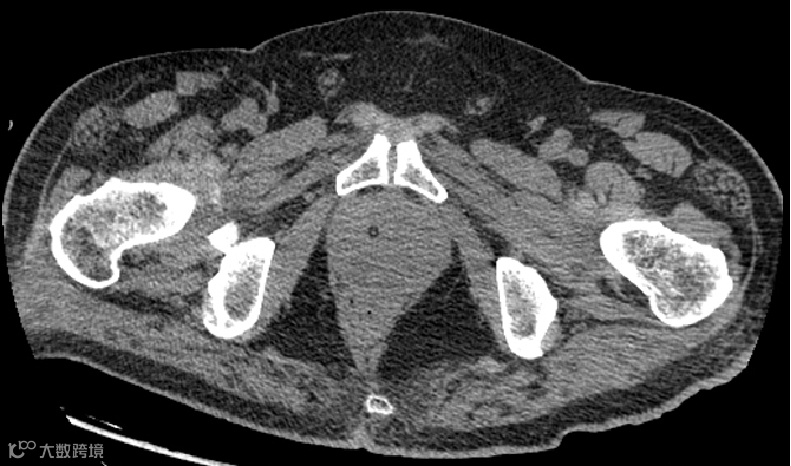

影像学表现